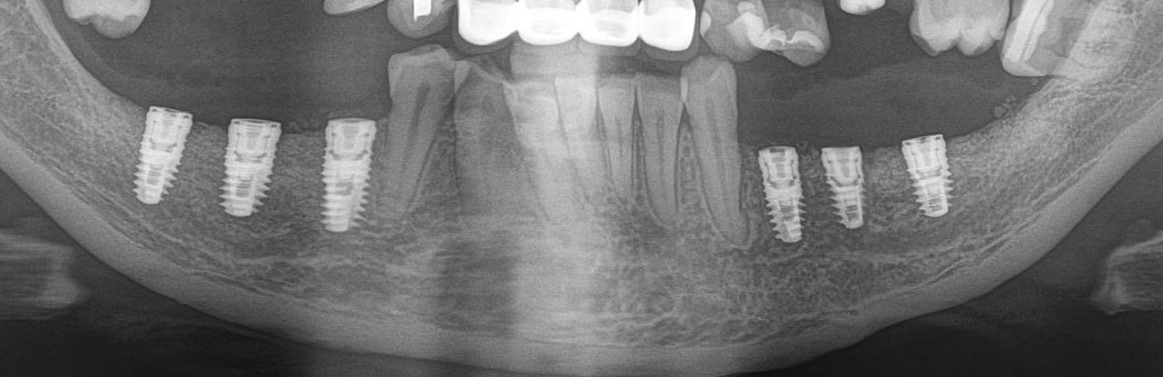

Рентгеновский снимок после операции (расщепление было проведено с двух сторон):

Снимок, сделанный через 5 месяцев после операции:

Обратите внимание, как изменился цвет кости. Она полностью восстановилась. На снимке этот участок стал белее.

Рентгеновский снимок после имплантации:

И спустя 3.5 месяца на этапе временных коронок (коронок не видно потому, что материал, из которого они изготавливаются, не рентгеноконтрастен):

Дружок в лице горизонтального зуба мудрости (на снимке справа) успешно был удалён.